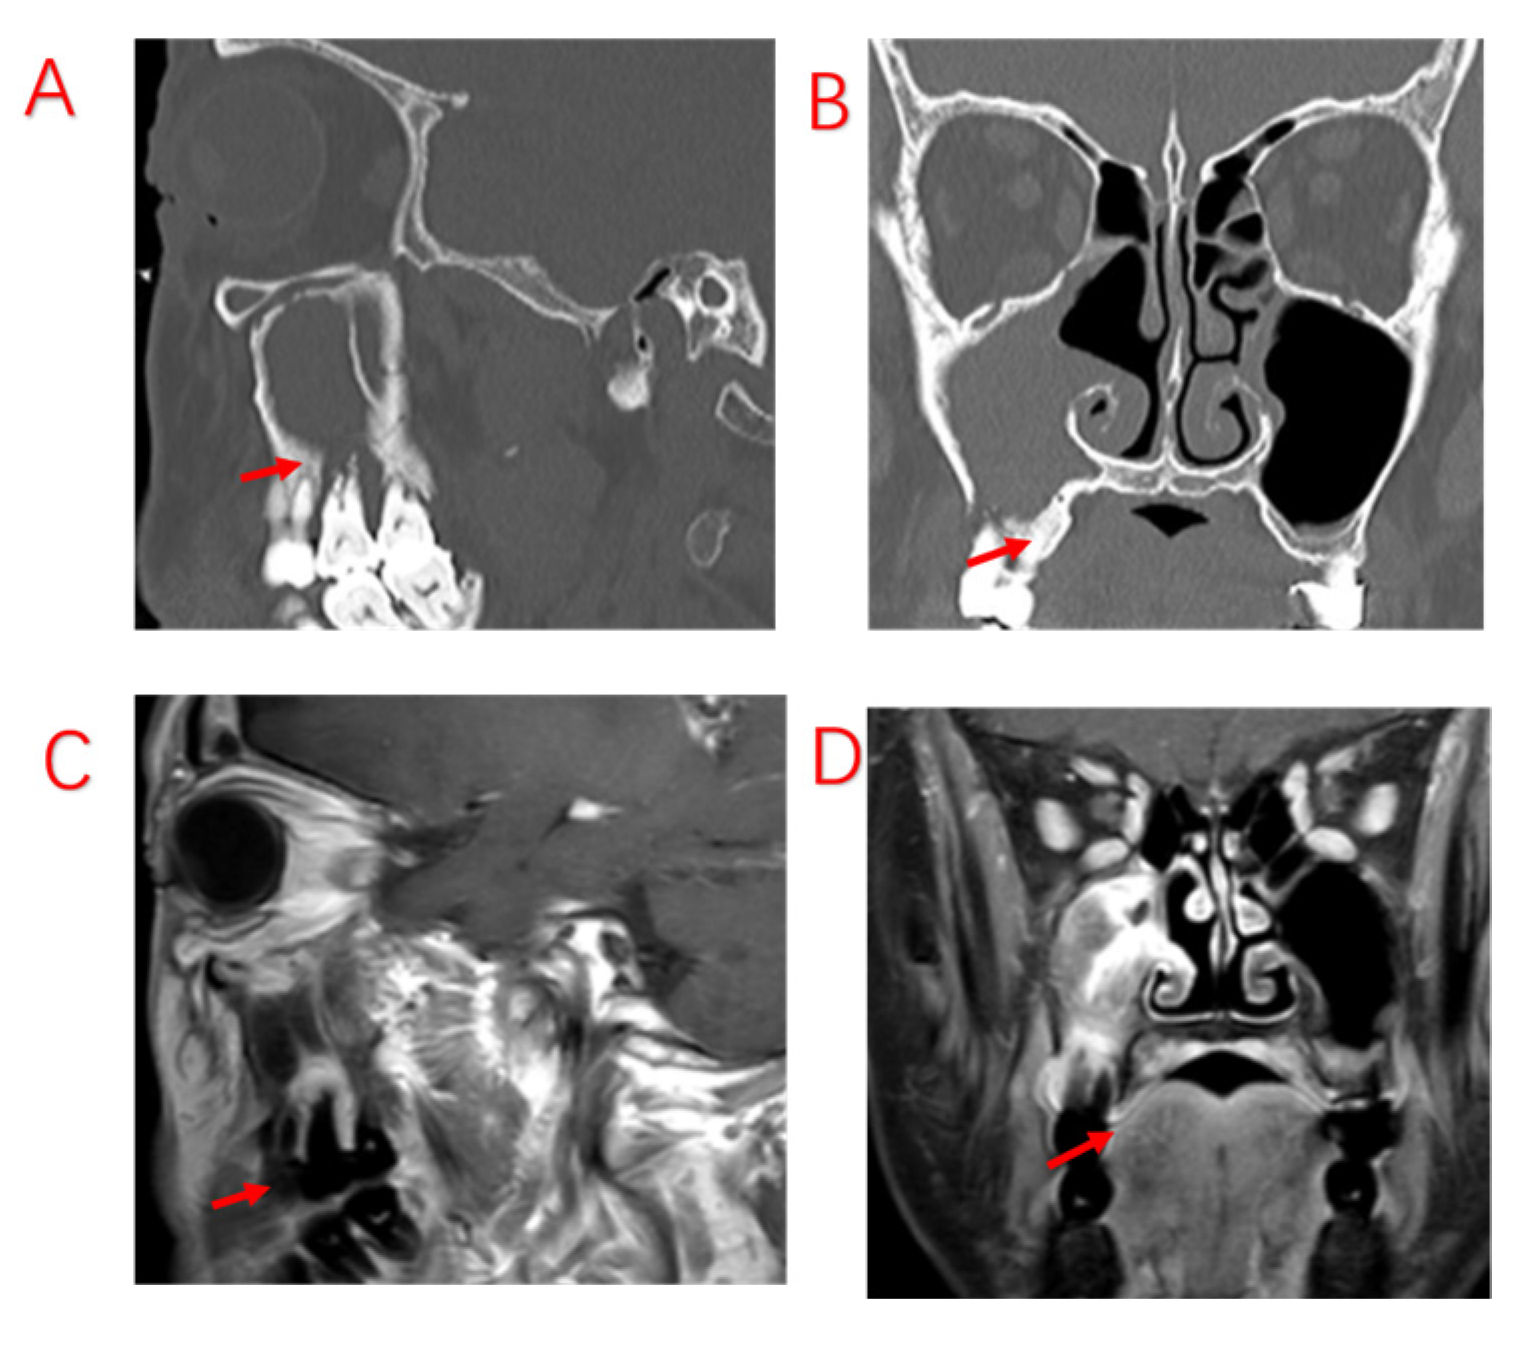

Figure 5.

Patient with severe periodontal infection and no improvement in sinusitis symptoms after ESS. (A,B): Sinus CT shows adequate maxillary sinus opening, alveolar bone resorption of the diseased tooth, and bone defects in the MSF. (C,D): MRI shows periodontal lesion tissue attached to the mucosa of the maxillary sinus, with significant swelling of the maxillary sinus mucosa. Red arrows indicate specific sites of bony defects in MSF.